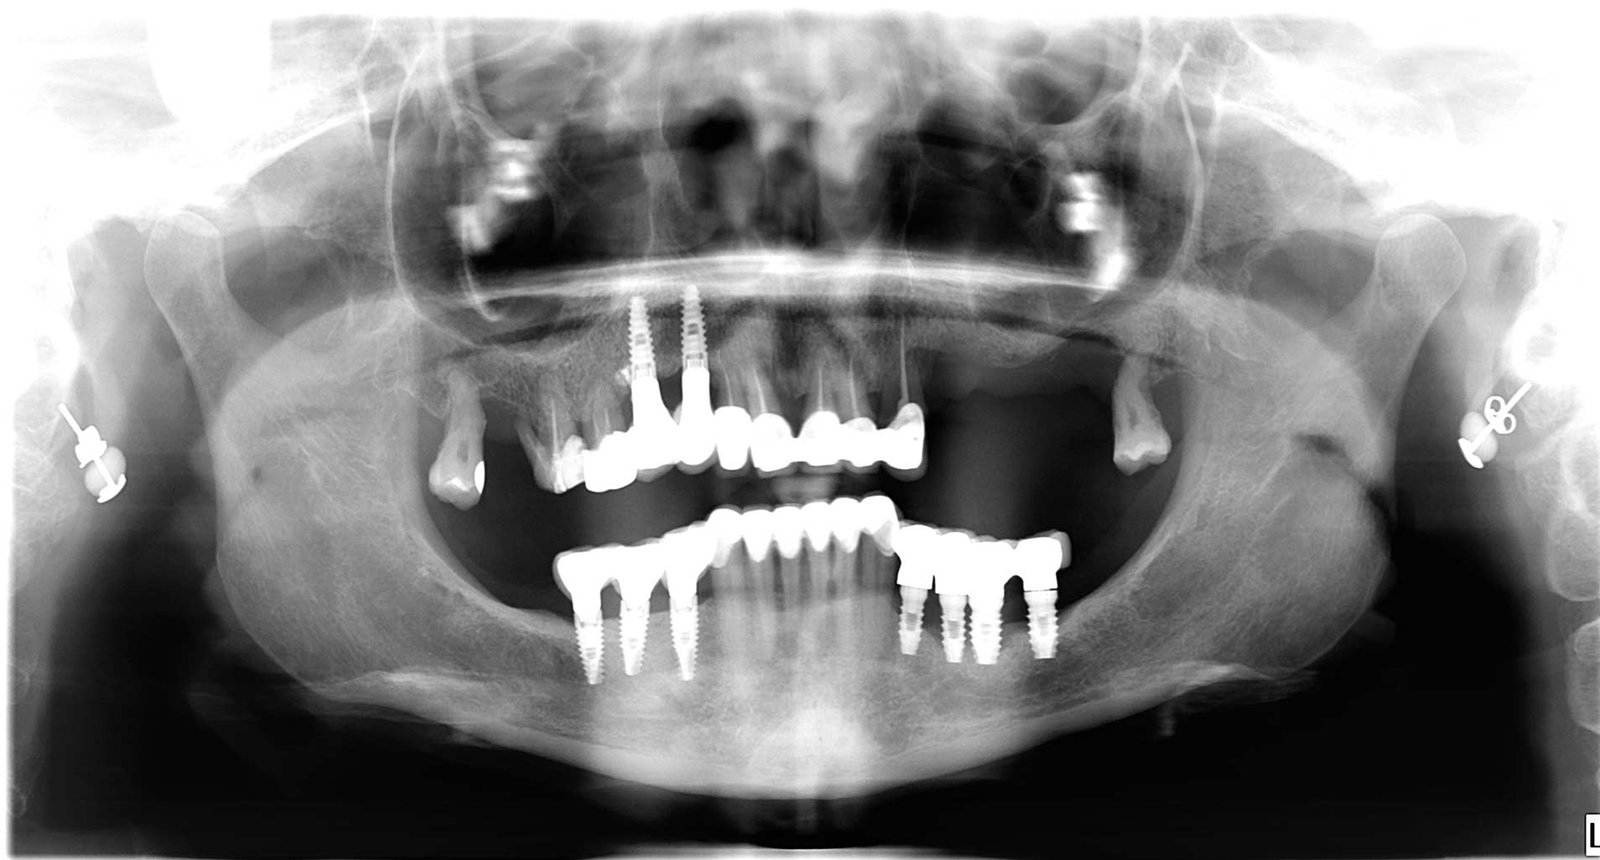

Caso 1 - caso de Implantes dentales

El paciente acudió a consulta con la ausencia de varias piezas dentales que dificultaban la masticación y afectaban a la estética de su sonrisa. Con la colocación de implantes dentales conseguimos recuperar dientes fijos, funcionales y de aspecto natural, devolviéndole seguridad y comodidad al sonreír.

En esta imagen se aprecia la ausencia de piezas dentales y el estado inicial del hueso, lo que permitió planificar un tratamiento implantológico preciso y seguro.